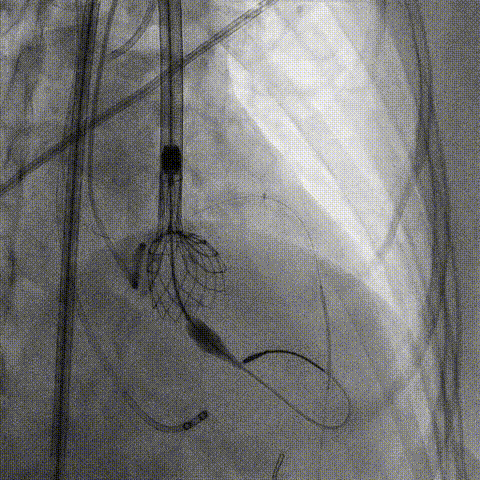

预置Telescope™导引延长导管及导丝保护左冠,

18mm球囊预扩张再次评估冠脉闭塞风险。

Telescope™+Runthrough

18mm*40mm 预扩张

预埋 Resolute Integrity 3.5*26mm

再次评估左冠开口

决定左冠烟囱支架保护冠脉

调整支架位置

释放冠脉支架

释放瓣膜

● TAVR术中,对于有冠脉风险的病人,冠脉保护是保证手术成功安全的重要环节。单用普通指引导管预留导丝是远远不够的,因瓣膜扩张或瓣架释放后,原生瓣膜的移位变形已经使原有冠脉开口情况发生变化,出现开口受压阻断等情況,经普通指引导管无法送入快速及时的置入支架、保护冠脉,故务必在置入辦膜前预先留置Telescope™于冠脉内,Telescope™头端位置务必进入冠脉开口内,保证Telescope™于冠脉内的稳定性,一旦开口受压,迅速经Telescope™送入支架,可选用“烟囱”等技术于冠脉开口释放支架,保证开口血流通畅。Telescope™独有的螺旋线圈技术灵活柔软可以深入冠脉;Smoothpass技术保证了支架置入的快速顺畅;头端柔软安全不损伤冠口,是TAVR术中冠脉保护不可或缺的重要器械。